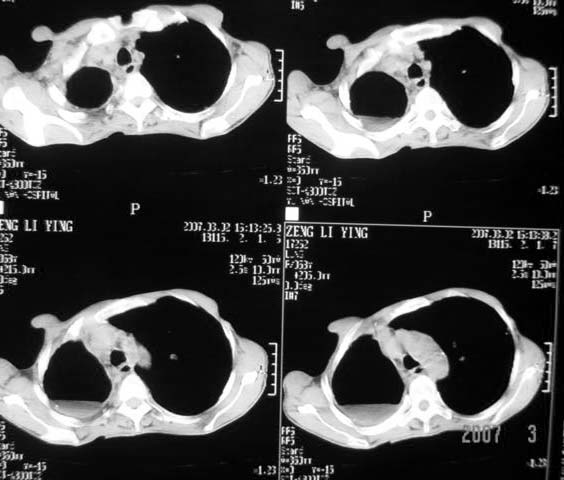

以下是引用dyqct在2007-3-2 22:04:00的发言:[br]考虑:1、右侧毁损肺伴支气管胸膜瘘(多条支气管与胸腔相通、液气胸);[br] 2、左肺浸润型肺结核。[br][br][br][br]